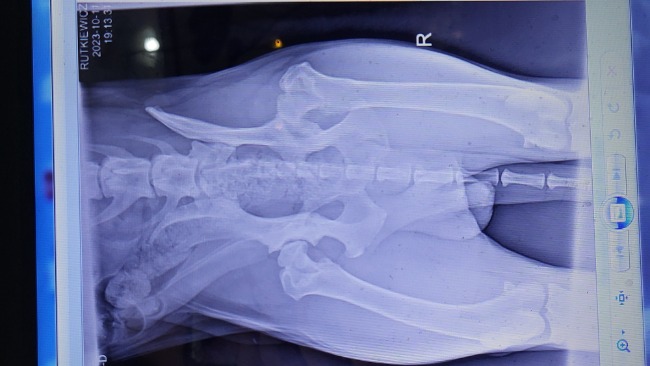

Niestety sprawdzenie hodowli i dokumentów nie wystarczyło 💔💔💔, ponieważ okazało się, że ma wadę genetyczną jaką jest dysplazja. Po konsultacji weterynaryjnej oraz zdjęciu RTG, okazało się, że Ares ma obustronną dysplazje😔. Choroba jest zaawansowana - po konsultacji z weterynarzem otrzymaliśmy informację, że Ares może przestać chodzić po ok 5 lub 6 roku życia 😥😭. Dlatego konieczne są 2 operacje (lewego i prawego biodra).